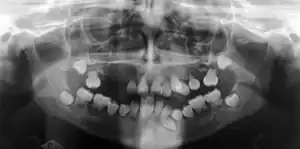

| Preoperative panoramic radiographs showing features of dentin dysplasia type I | |

In other words, affected primary teeth usually have abnormal shaped or shorter than normal roots. “Crescent/half-moon shaped” pulp chamber remnant in permanent teeth can be seen on x-rays. The roots may appear to be darker or radiolucent/pointy and short with apical constriction. Dentine is laid down abnormally and causes excessive growth within the pulp chamber. This will reduce the pulp space and eventually cause incomplete and total pulp chamber obliteration in permanent teeth.[12][13] Sometimes periapical pathology or cysts can be seen around the root apex.[11] Most cases of DD associated with peri-apical radiolucency/ pathology have been diagnosed as radicular cysts, but some of them have been as diagnosed peri-apical grauloma instead.[14]